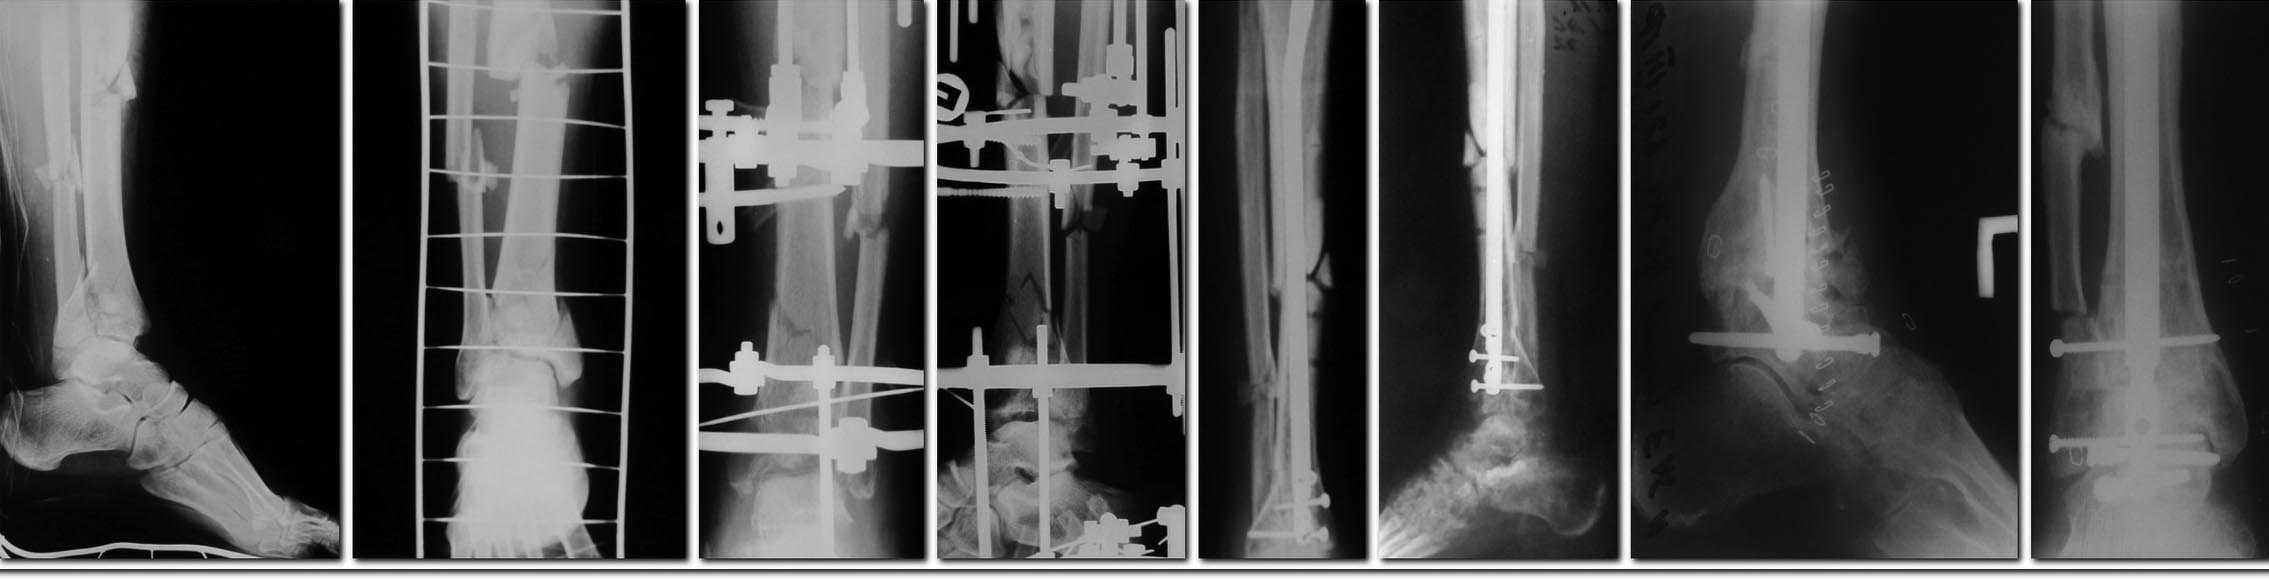

У больного, в составе множественной травмы конечностей, имелся фрагментарный перелом обеих костей голени (42В2, 43С3). Выполнен остеосинтез аппаратом Илизарова.

На рентгенограммах осенью 2012 года имеется несросшийся перелом правой большеберцовой кости в средней трети, перелом нижней трети консолидирован. По поводу несросшегося перелома выполнен демонтаж аппарата Илизарова, остеосинтез штифтом "Эксперт". Впоследствии, у больного имелись боли в голеностопном суставе (при ходьбе и в покое), ограничение амплитуды движений, на рентгенограммах определяется несросшийся перелом диафиза большеберцовой кости.

В связи с чем, в январе 2014 года больному удален штифт, выполнено рассверливание костномозгового канала, реостеосинтез штифтом большего диаметра, артродез правого голеностопного сустава, с костной пластикой. Раны зажили без воспаления. В течение 4х недель после операции передвигался с опорой на костыли, с нагрузкой 25 кг. Сейчас передвигается с опорой 50 кг на правую ногу.